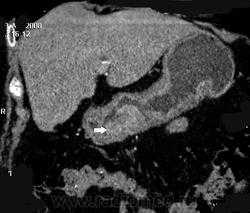

Однако наиболее распространенным является применение КТ для диагностики и дифференциальной диагностики очаговых поражений печени и поджелудочной железы. Стандартным является выполнение КТ с болюсным введением 100-140 мл контрастного средства. Многофазное исследование в различные фазы контрастирования (из которых важнейшими являются артериальная и портально-венозная) позволяет выявлять и характеризовать очаговые поражения печени и поджелудочной железы, планировать лечение и оценивать его результаты. С помощью МСКТ можно с высокой точностью визуализировать артерии и вены органов брюшной полости, а также желчные протоки.

Благодаря быстроте и надежности МСКТ все чаще используется при обследовании пациентов с диагнозом «острый живот» (выявление перфорации полых органов, кровотечений, кишечной непроходимости, мезентериальной ишемии, острого аппанедицита, панкреатита, холецистита и другой патологии).